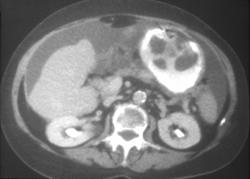

Subtle Gastric Cancer With Liver Metastases